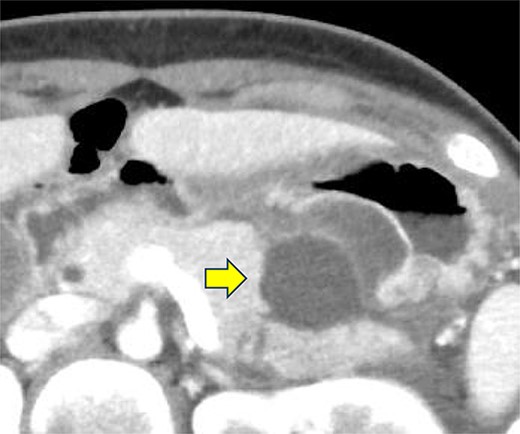

On the fifth day, the ascitic fluid increased in volume, and an open distal pancreatectomy was considered. However, her condition was stable. CT-guided abdominal drainage was performed, and a 10 Fr drainage tube was inserted for peritoneal lavage (Fig. 4). EUS-guided transgastric drainage of the pseudocyst in the omental bursa was performed. The pseudocyst was punctured; a balloon was dilated through the posterior wall of the stomach (Fig. 5a–c), and three tube stents of 7 Fr were implanted (Fig. 5d). The Amy and P-Amy levels in ascites were 9429 and 8877 IU/L, respectively; then, peritoneal lavage was performed daily. On the 12th day, contrast-enhanced CT revealed reduced pseudocyst size (Fig. 6). The patient was discharged on the 16th day (Fig. 7). Three years later, the patient is living her daily life without any complications.

Contrast-enhanced CT on the 12th day. The pseudocyst in the omental bursa had shrunk. The arrow indicates the pseudocyst.